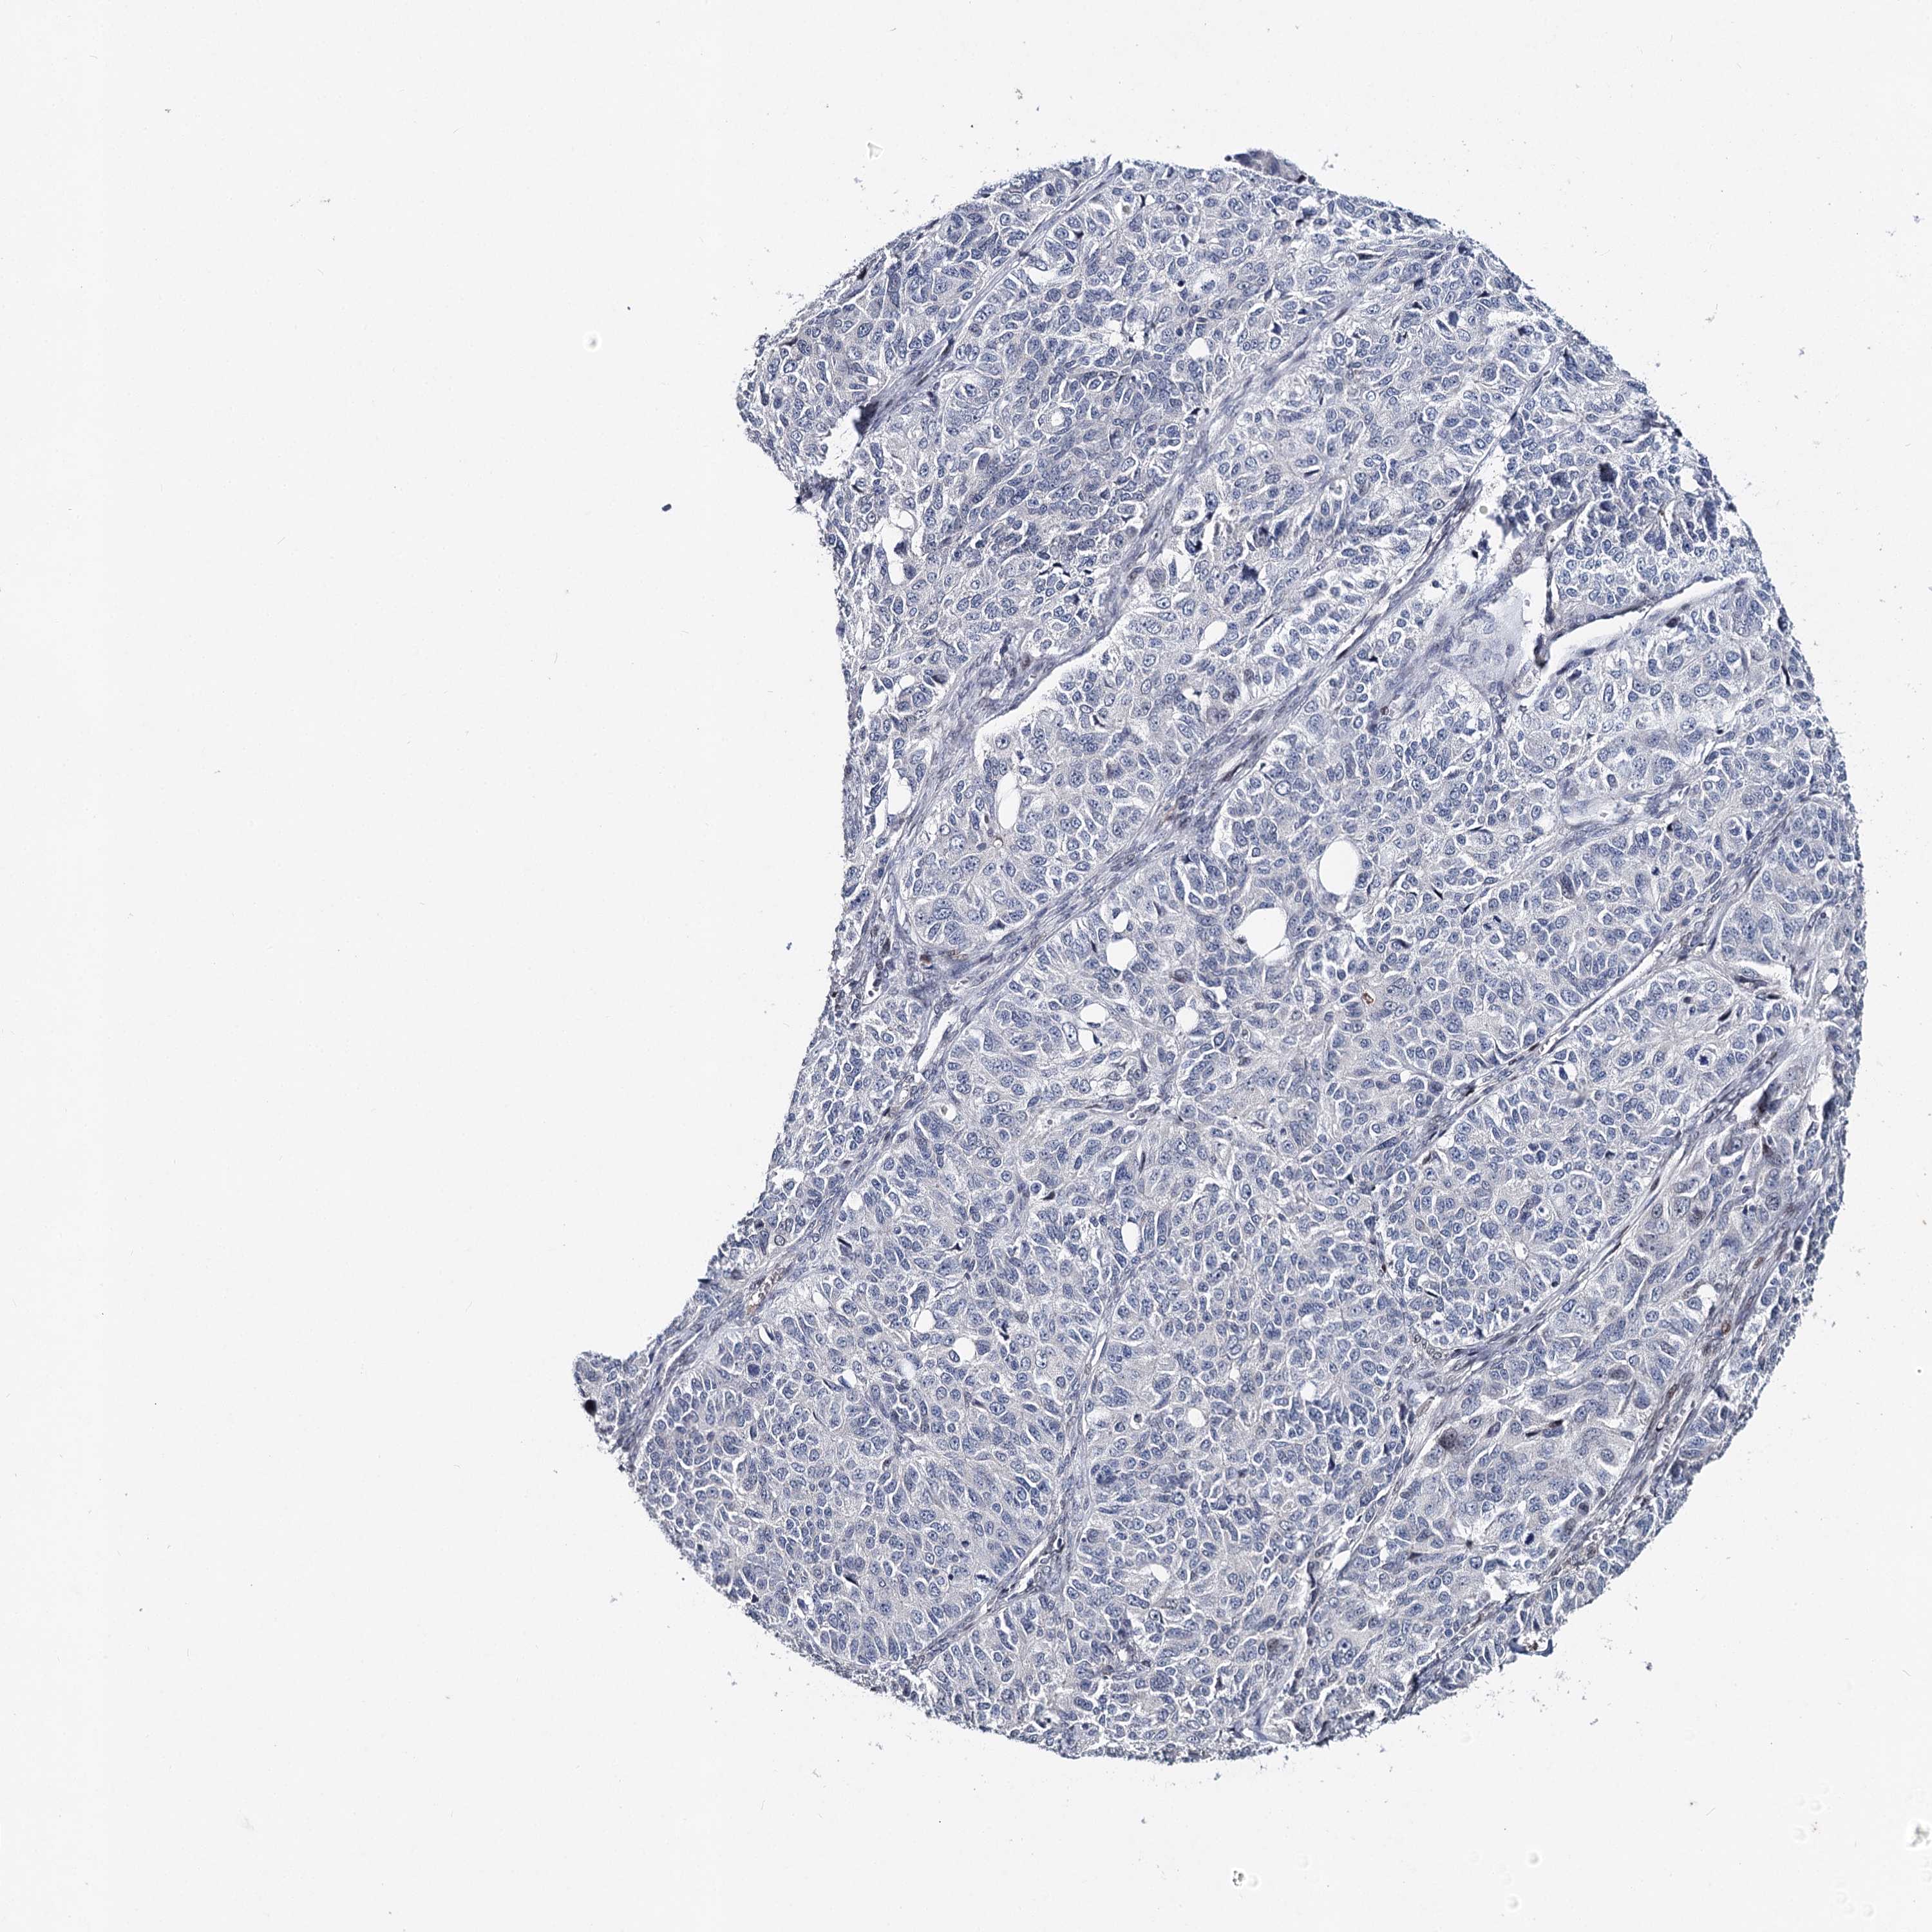

OVARIAN CANCER - Protein expressioni

A mouse-over function shows sample information and annotation data. Click on an image to view it in a full screen mode. Samples can be filtered based on level of antibody staining by selecting one or several of the following categories: high, medium, low and not detected. The assay and annotation is described here.

Note that samples used for immunohistochemistry by the Human Protein Atlas do not correspond to samples in the TCGA dataset.

Antibody stainingi

Antibody staining in the annotated cell types in the current human tissue is reported as not detected, low, medium, or high, based on conventional immunohistochemistry profiling in selected tissues. This score is based on the combination of the staining intensity and fraction of stained cells.

Each image is clickable and will lead to virtual microscopy that enables deeper exploration of all samples and also displays staining intensity scores, fraction scores and subcellular localization as well as patient and tissue information for each sample.

Antibody HPA038449

Staining

High

Medium

Low

Not detected

Intensity

Strong

Moderate

Weak

Negative

Quantity

>75%

75%-25%

<25%

None

Location

Nuclear

Cytoplasmic/membranous

Cytoplasmic/membranous,nuclear

Cystadenocarcinoma, serous, NOS

Carcinoma, endometroid

Cystadenocarcinoma, mucinous, NOS

Carcinoma, NOS